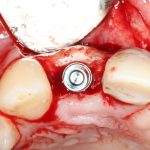

Глянем на то, что получилось:

Осталось адаптировать костный блок (убрать острые края), проверить его фиксацию и, при необходимости, добавить винты. Десятисекундное дело.

Изоляция области аутографта и имплантатов барьерной мембраной.

Перекрывать костный блок барьерной мембраной или оставить так? По этому вопросу есть много мнений. Между тем, в публикации по методике есть ясное показание, когда это требуется.

Конкретно в этом клиническом случае между костным аутотрансплантатом, ложем и имплантатами есть пустое пространство. Если его не изолировать от мягких тканей, они прорастут и осложнят интеграцию аутографта. Поэтому я решил перекрыть костный блок барьерной мембраной, пусть это делает хирургическую операцию немного дороже.